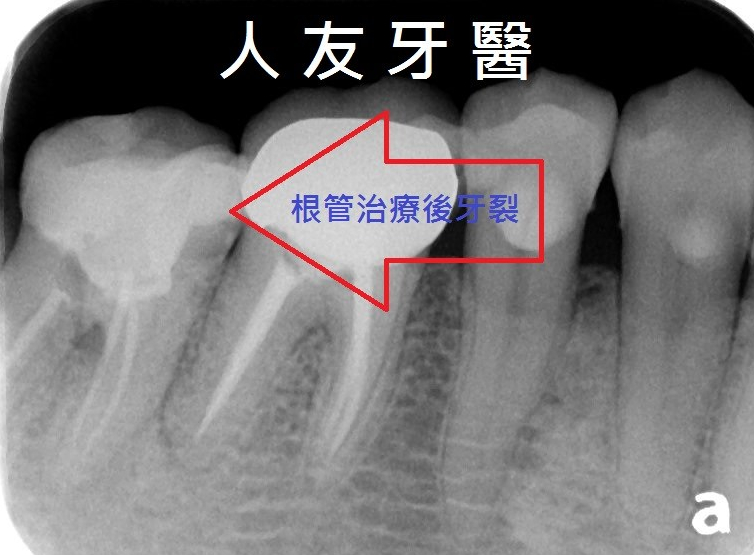

解決根管治療後遺症的好方法